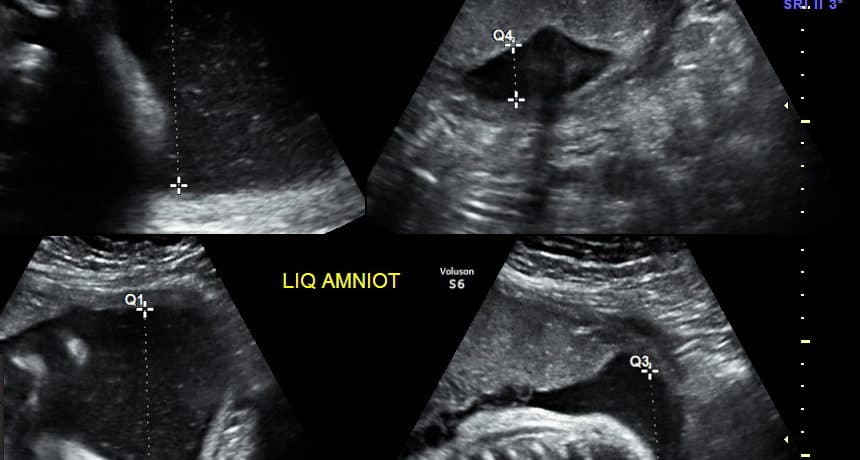

No período pré-natal, o peso fetal estimado pela ultrassonografia é usado junto com as tabelas de peso para avaliar o…